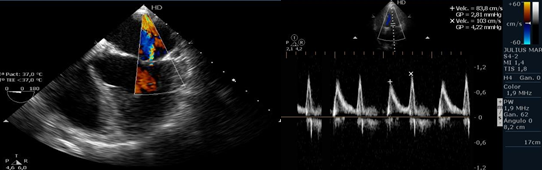

Curso Anual de Ecocardiografía Doppler con Formación Técnica

Este curso está diseñado para formar técnicos en ecocardiografía con un enfoque práctico y técnico, capaces de colaborar activamente en la adquisición de imágenes cardíacas de alta calidad para su análisis por el cardiólogo especialista.